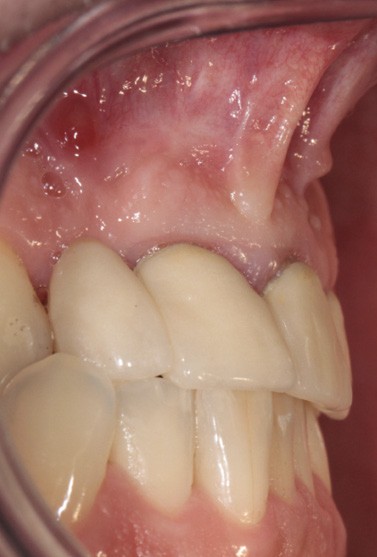

L’examen endobuccal montre deux fistules en regard des apex de 12 et 21 (fig. 1). Nous notons la présence d’une classe III squelettique, d’une occlusion inversée du côté droit (fig. 2) et des édentements non compensés au niveau de 26 et 36. L’orthopantomogramme révèle la présence d’une volumineuse lésion kystique qui s’étend de la 12 à la 22 (fig. 3).